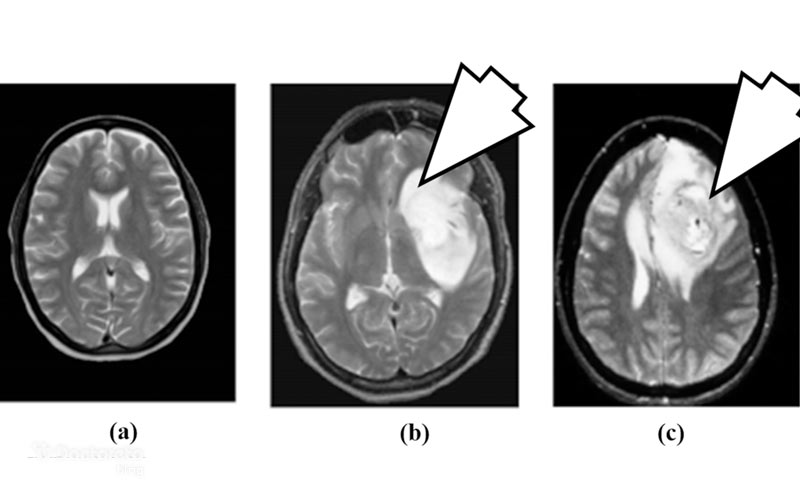

عکس تصویربرداری های تومور مغزی بدخیم

در MRI بافت مغز وضوح بالاتری دارد و برای بررسی تومورهای مغزی ارجح است و میتواند تفاوت بین بافت سالم، بافت متورم و نواحی سرطانی را با وضوح بالا نشان دهد. در این تصاویر، تومورهای بدخیم معمولاً بهصورت نواحی با مرز نامشخص، رشد سریع و گاه با بخشهای مرکزی نکروزه دیده میشوند. استفاده از ماده حاجب در MRI باعث میشود نواحی فعالتر تومور که اختلال سد خونی–مغزی دارند، با الگوی تقویت کنتراست واضحتر دیده شوند.

از سوی دیگر، سی تی اسکن نیز در شرایط اورژانسی یا زمانی که MRI در دسترس نیست، کاربرد دارد. این روش بهویژه برای شناسایی خونریزی، تورم مغز یا اثرات فشاری تومور بر ساختارهای اطراف مفید است. در برخی موارد، پزشکان از روشهای پیشرفتهتر مانند PET Scan یا fMRI نیز استفاده میکنند تا فعالیت متابولیک تومور و عملکرد بخشهای حیاتی مغز را بررسی کنند. ترکیب این روشها به تشخیص دقیقتر نوع، محل و شدت تومور بدخیم کمک میکند.

عکس mri تومور مغزی بدخیم

MRI با استفاده از میدان مغناطیسی و امواج رادیویی، تصاویر دقیق از بافت مغز و تومور ارائه میدهد. این تصاویر به پزشک کمک میکنند میزان نفوذ تومور به بافتهای اطراف، فشار روی بطنها و محل خونریزی داخل تومور را تشخیص دهد. در بسیاری از موارد، ام ار ای با تزریق ماده حاجب (Contrast) انجام میشود تا مرزهای تومور واضحتر و تمایز بین بافت سالم و سرطانی مشخص شود. این اطلاعات برای جراحی و برنامهریزی درمان هدفمند بسیار مهم هستند.

MRI machines use powerful magnets and radio waves to create detailed images of the brain. This helps doctors find and check the tumor.

دستگاههای MRI از آهنرباهای قوی و امواج رادیویی برای ایجاد تصاویر دقیق از مغز استفاده میکنند. این تصاویر به پزشکان کمک میکند تا محل تومور را شناسایی کرده و وضعیت آن را بهطور دقیق بررسی کنند.